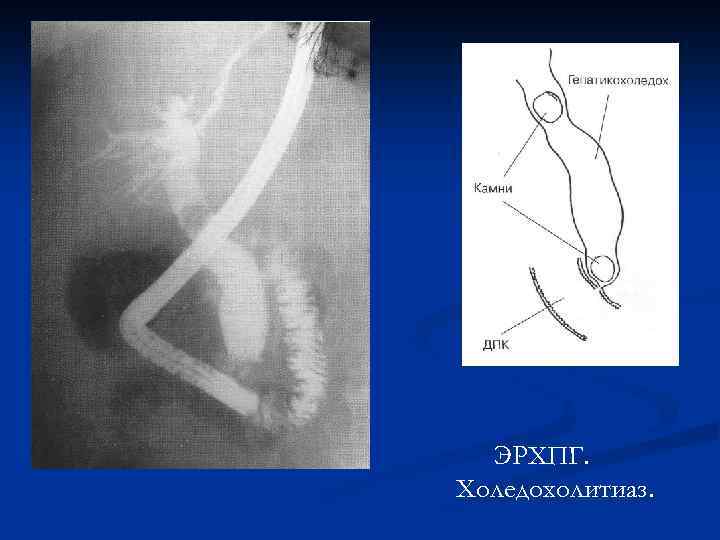

ЭРХПГ. Холедохолитиаз.

ЭРХПГ. Холедохолитиаз.

ЭРХПГ. Холедохолитиаз.

ЭРХПГ. Холедохолитиаз.